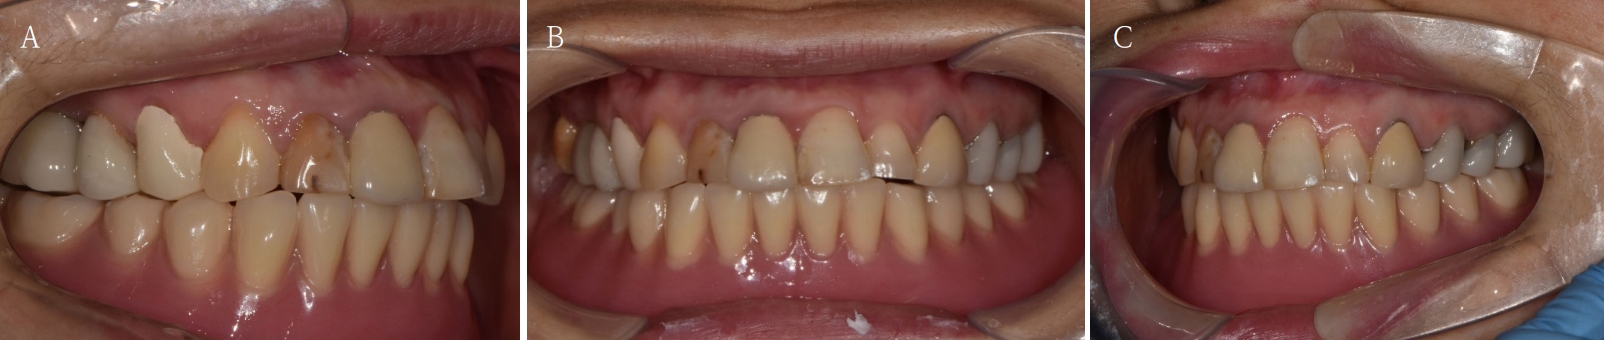

Fig. 14.

The final prosthesis is functionally and esthetically fitted with the patient. A. Right side view. B. Frontal view. C. Left side view.

jkda-2025-63-7-001f14.jpg

최종 보철물은 양측 최후방 임플란트 고정체에 각각 Ti-base(TS multi Ti base, Osstem, Seoul, Korea)와 접착된 나사 유지형 단일 지르코니아 크라운으로, 지르코니아 블록(Zircen, Kuwotech, Gwangju, Korea)을 밀링하여 제작하였고, 치경부 하방으로 포세린으로 치은 형태를 부여하였다. 전방부 3개의 임플란트 고정체에는 맞춤형 지대주를 제작하여 30N으로 체결하였고, 양측 최후방 고정체는 20Ncm으로 체결한 후 레진 시멘트(Rely X U200; 3M ESPE, St. Paul, MN, USA)로 접착 시행하였다. 장착 후 중심교합시 양측의 제1대구치 부위에서 교합력이 적게 가해지도록 교합 조정 시행하였으며, 전방과 측방운동시에 임플란트 상호보호교합이 되도록 조정하였다. 또한 연결부 하방으로 치실을 통과시켜 치은 점막 사이 공간을 평가하였으며, 구강 위생 관리의 용이성을 확인하였다. 이후 1주, 1개월, 3개월 경과 관찰하였고, 환자는 저작이나 심미, 발음 등에서 만족해하였다(Figs. 14 and 15).